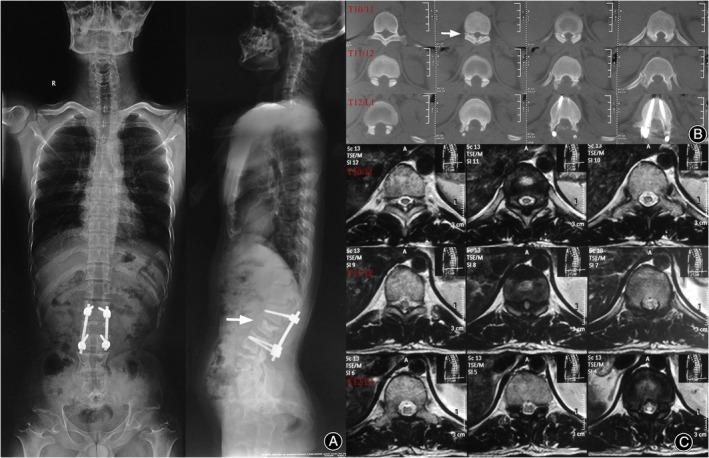

Seven patients were included in this series. The mean preoperative VAS was 4, and the mean preoperative ODI was 50.98%. All patients had concomitant spinal stenosis, four with thoracolumbar kyphosis (TLK), and one with scoliosis. Six of the seven patients underwent surgery, and one patient received conservative treatment. In the routine follow-ups, all patients experienced satisfactory relief of symptoms. Only one of the seven patients developed a new rare lesion adjacent to the primary segments. Six months after the first surgery, a follow-up visit revealed thoracic spinal stenosis caused by ossification of the ligamentum flavum, and his symptoms were relieved after thoracic decompression surgery.

本系列研究共纳入 7 例患者。术前 VAS 平均为 4,术前 ODI 平均为 50.98%。所有患者均合并有脊柱狭窄,其中 4 例合并胸腰椎后凸(TLK),1 例合并脊柱侧凸。7 例患者中 6 例行手术治疗,1 例患者行保守治疗。在常规随访中,所有患者的症状均得到了满意的缓解。仅有 1 例患者在原发节段附近出现新的罕见病变。初次手术后 6 个月,患者因黄韧带骨化导致胸段椎管狭窄,行胸椎减压手术后症状缓解。